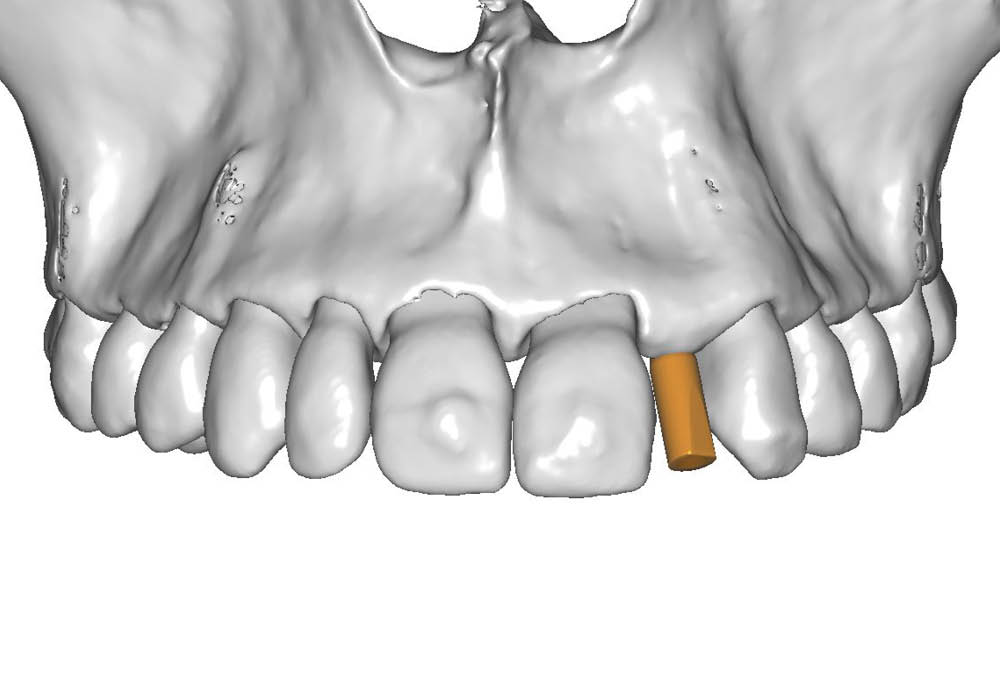

Il primo passaggio ha previsto la valutazione dell’area edentula e la pianificazione implantare.

In questo caso, la particolarità è rappresentata dalla scarsa distanza tra la posizione ideale dell’impianto e le radici degli elementi adiacenti, un aspetto che ha richiesto massima attenzione nella scelta dell’asse e nella valutazione dei volumi disponibili.

La pianificazione chirurgica ha previsto un’analisi tridimensionale dettagliata del sito implantare, valutato sia da angolazioni multiple sia in visione frontale diretta.

L’obiettivo era quello di definire con precisione posizione, profondità e inclinazione dell’impianto, tenendo conto della vicinanza delle radici adiacenti e della necessità di preservare un adeguato spessore vestibolare.

Questa fase ha permesso di anticipare eventuali criticità e assicurare l’inserzione corretta all’interno dei limiti anatomici disponibili.